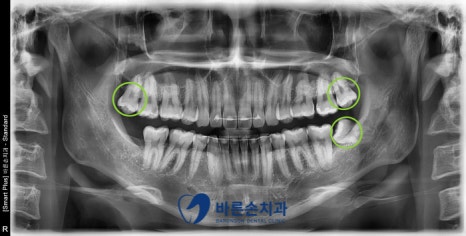

전체 검사 결과,

충치치료 2개와 사랑니 발치가 필요하다는 진단이 나왔습니다.

사진에서 보시면

★ 오른쪽 위 두번째 큰 어금니는 인접면 우식이 심하게 진행 -> 신경치료와 크라운

■ 오른쪽 아래 첫번째 큰 어금니의 교합면 우식 -> 인레이

● 오른쪽 위와 왼쪽 위아래 사랑니의 교합면 우식 -> 발치

치료가 필요한 상황입니다.